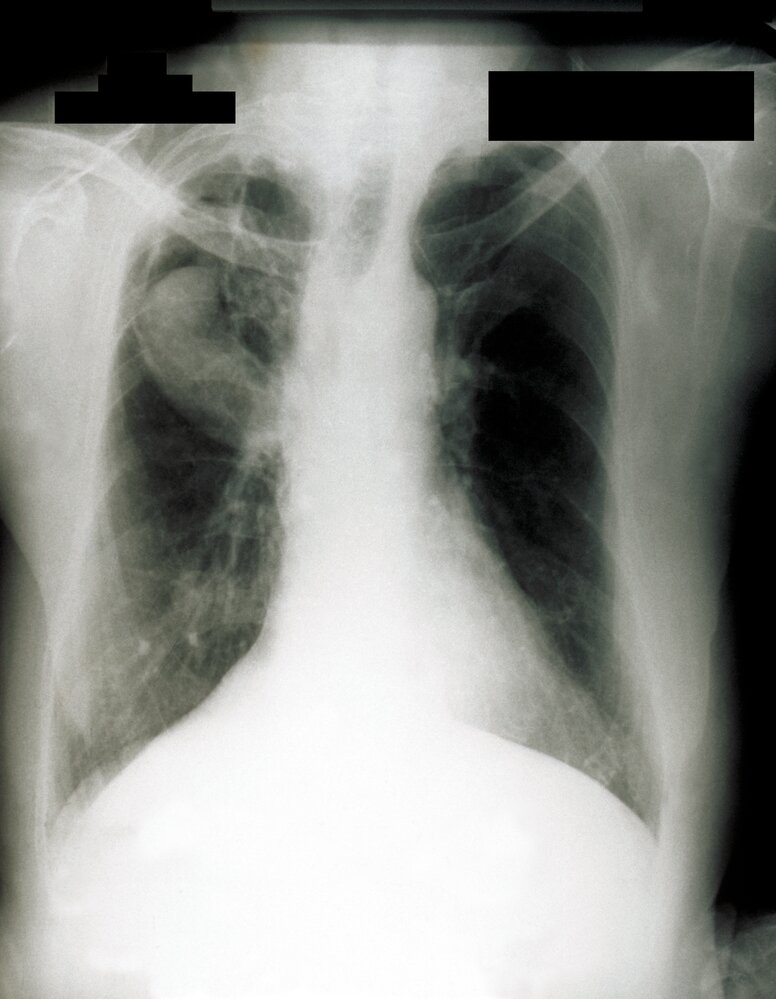

Chest imaging [7][8]

• Chest x-ray (initial test)

• CTA of the thorax if there are findings of CPA on chest x-ray

• Findings include:

• Chronic cavitary pulmonary aspergillosis: one or more cavities, often with irregular intraluminal material and/or aspergilloma, pericavitary infiltrates, and/or pleural thickening [4]

• Aspergilloma

• Mobile fungus ball (visible when the patient is moved from a supine position to a prone or lateralrecumbent position)

• Monod sign: a peripheral air crescent surrounding a fungus ball in a preexisting lung cavity

• The upper lobe is most commonly affected

• Aspergillus nodule: one or more nodules (may be cavitated), frequently necrotic

• Chronic fibrosing pulmonary aspergillosis: cavities and extensive fibrosis

• Subacute invasive aspergillosis: cavities, nodules, and/or consolidations with abscess formation